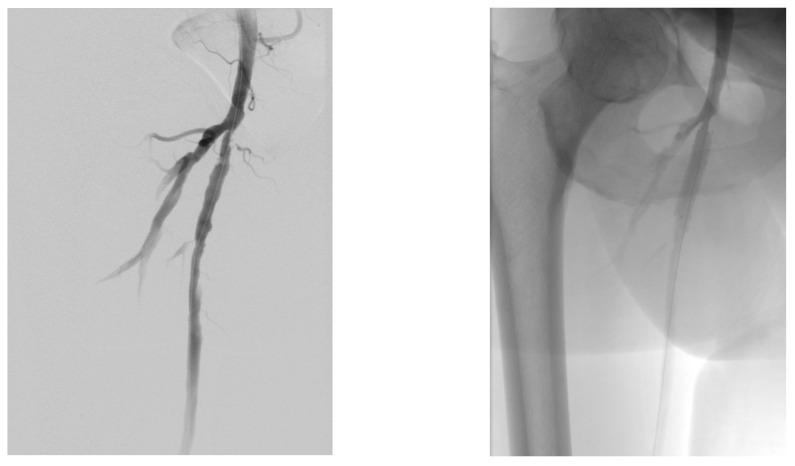

: Revascularization based on the angiosome concept (AC) is a controversial subject because there is currently no clear evidence of its efficacy, due to the heterogeneity of patients (multiple and diverse risk factors and comorbidities, multiple variations in the affected angiosomes). Choke vessels change the paradigm of the AC, and the presence or absence of the plantar arch directly affects the course of targeted revascularization. The aim of this study was to evaluate the effect of revascularization based on the AC in diabetic patients with chronic limb-threatening ischemia (CLTI). This retrospective analysis included 51 patients (40 men, 11 women), with a mean age of 69 years (66-72) and a total of 51 limbs, who presented with Rutherford 5-6 CLTI, before and after having undergone a drug-coated balloon angioplasty (8 patients) or plain balloon angioplasty (43). Between November 2018 and November 2019, all patients underwent below-the-knee balloon angioplasties and were followed up for an average of 12 months. The alteration of microcirculation was compared between directly and indirectly revascularized angiosomes. The study assessed clinical findings and patient outcomes, with follow-up investigations, comparing wound healing rates between the different revascularization methods. Patient records and periprocedural leg digital subtraction angiographies (DSA) were analyzed. Differences in outcomes after direct revascularization and indirect percutaneous transluminal angioplasty (PTa) were examined using Cox proportional hazards analysis, with the following endpoints: ulcer healing, limb salvage, and also amputation-free survival. Direct blood flow to the angiosome supplying the ulcer area was achieved in 38 legs, in contrast to 13 legs with indirect revascularization. Among the cases, there were 39 lesions in the anterior tibial artery (ATA), 42 lesions in the posterior tibial artery (PTA), and 8 lesions in the peroneal artery (PA). According to a Cox proportional hazards analysis, having fewer than three (<3) affected angiosomes (HR 0.49, 95% CI 0.19-1.25, = 0.136) was associated with improved wound healing. Conversely, wound healing outcomes were least favorable after indirect angioplasty ( = 0.206). When adjusting the Cox proportional hazard analysis for the number of affected angiosomes, it was found that direct drug-coated angioplasty resulted in the most favorable wound healing ( = 0.091). At the 1-year follow-up, the major amputation rate was 17.7%, and, according to a Cox proportional hazards analysis, atrial fibrillation (HR 0.85, 95% CI 0.42-1.69, = 0.637), hemodialysis (HR 1.26, 95% CI 0.39-4.04, = 0.699), and number of affected angiosomes > 3 (HR 0.94, 95% CI 0.63-1.39, = 0.748) were significantly associated with poor leg salvage. Additionally, direct endovascular revascularization was associated with a lower rate of major amputation compared to indirect angioplasty (HR 1.09, 95% CI 0.34-3.50, = 0.884). Observing the angiosomes concept in decision-making appears to result in improved rates of arterial ulcer healing and leg salvage, particularly in targeted drug-coated balloon angioplasty for diabetic critical limb ischemia, where multiple angiosomes are typically affected.

基于血管体概念(AC)的血运重建是一个有争议的话题,因为目前尚无明确证据证明其疗效,这是由于患者存在异质性(多种不同的风险因素和合并症,受累血管体存在多种变异)。窒息血管改变了AC的模式,足底弓的存在与否直接影响靶向血运重建的进程。本研究的目的是评估基于AC的血运重建对慢性肢体威胁性缺血(CLTI)糖尿病患者的影响。这项回顾性分析纳入了51例患者(40例男性,11例女性),平均年龄69岁(66 - 72岁),共51条肢体,这些患者在接受药物涂层球囊血管成形术(8例)或普通球囊血管成形术(43例)前后均表现为卢瑟福5 - 6级CLTI。在2018年11月至2019年11月期间,所有患者均接受了膝下球囊血管成形术,并平均随访12个月。比较了直接和间接血运重建血管体之间的微循环变化。该研究评估了临床发现和患者预后,并通过随访调查比较了不同血运重建方法之间的伤口愈合率。分析了患者记录和围手术期腿部数字减影血管造影(DSA)。使用Cox比例风险分析检查直接血运重建和间接经皮腔内血管成形术(PTa)后结局的差异,终点如下:溃疡愈合、肢体挽救以及无截肢生存率。38条腿实现了向供应溃疡区域的血管体的直接血流,相比之下,13条腿为间接血运重建。在这些病例中,胫前动脉(ATA)有39处病变,胫后动脉(PTA)有42处病变,腓动脉(PA)有8处病变。根据Cox比例风险分析,受累血管体少于三个(<3)(HR 0.49,95%CI 0.19 - 1.25,P = 0.136)与伤口愈合改善相关。相反,间接血管成形术后伤口愈合结局最不理想(P = 0.206)。在对受累血管体数量进行Cox比例风险分析调整后,发现直接药物涂层血管成形术导致最有利的伤口愈合(P = 0.091)。在1年随访时,大截肢率为17.7%,根据Cox比例风险分析,心房颤动(HR 0.85,95%CI 0.42 - 1.69,P = 0.637)、血液透析(HR 1.26,95%CI 0.39 - 4.04,P = 0.699)以及受累血管体数量>3(HR 0.94,95%CI 0.63 - 1.39,P = 0.748)与肢体挽救不佳显著相关。此外,与间接血管成形术相比,直接血管内血运重建与较低的大截肢率相关(HR 1.09, 95%CI 0.34 - 3.50, P = 0.884)。在决策过程中遵循血管体概念似乎能提高动脉溃疡愈合率和肢体挽救率,特别是在针对糖尿病严重肢体缺血的靶向药物涂层球囊血管成形术中,此时多个血管体通常会受累。